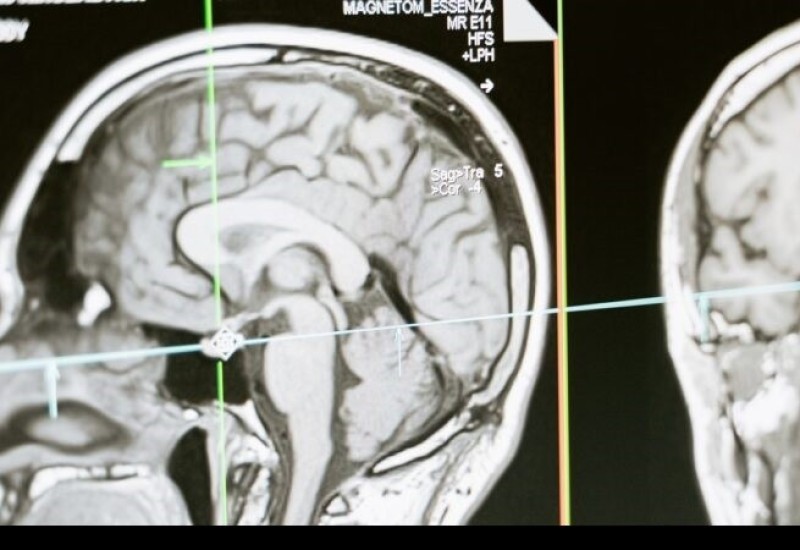

Zapanjujuća otkrića: Naučnici snimili šta se dešava u mozgu osobe na samrti

Organizator studije dr Ajmal Zemar, neurohirurg sa Univerziteta u Luisvilu, kaže da bi to moglo značiti da je ideja da nam život „proleti pred očima dok umiremo“ utemeljena u nauci.

– Nešto što možemo da naučimo iz ovog istraživanja jeste sljedeće: iako naši voljeni imaju zatvorene oči i spremni su da nas napuste, njihov mozak možda ponavlja neke od najljepših trenutaka koje su doživjeli u životu – dodao je dr Zemar.